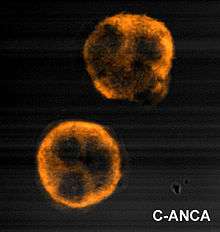

ANCA IF patterns

Immunofluorescence (IF) on ethanol-fixed neutrophils is used to detect ANCA, although formalin-fixed neutrophils may be used to help differentiate ANCA patterns. ANCA can be divided into four patterns when visualised by IF; cytoplasmic ANCA (c-ANCA), C-ANCA (atypical), perinuclear ANCA (p-ANCA) and atypical ANCA (a-ANCA), also known as x-ANCA. c-ANCA shows cytoplasmic granular fluorescence with central interlobular accentuation. c-ANCA (atypical) shows cytoplasmic staining that is usually uniform and has no interlobular accentuation. p-ANCA has three subtypes, classical p-ANCA, p-ANCA without nuclear extension and granulocyte specific-antinuclear antibody (GS-ANA). Classical p-ANCA shows perinuclear staining with nuclear extension, p-ANCA without nuclear extension has perinuclear staining without nuclear extension and GS-ANA shows nuclear staining on granulocytes only. a-ANCA often shows combinations of both cytoplasmic and perinuclear staining.[1]